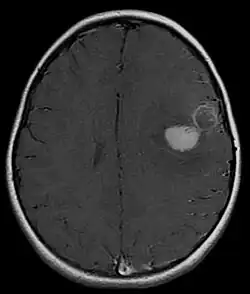

Several analysis can be used to determine the presence of the disease. Physical examinations showing papilledema, visual field defects, cranial nerves palsy, dysphasia, and focal neurological deficits are evidences for possible tumor.[2] PNETs can also be spotted through computed tomography (CT) and magnetic resonance imaging (MRI).[2] In images produced by MRIs, an irregular augmentation among a solid mass will indicated the presence of tumor.[3] However, the results of MRIs are usually ambiguous in defining the presence for this specific tumor.[2] In CT scans, the presence of PNETs will be indicated by an elevated density and an increase in volume of the brain.[2] The CT scan can also show calcification,[3] which is present in 41-44% of PNET cases.[2] Since the tumor can be replicated in other parts of the nervous system through the cerebrospinal fluid (CSF), a CSF analysis can also be conducted.[2] A spinal MRI is a fourth type of analysis that is useful in investigating the level of tumor propagation to the spinal cord.[2]